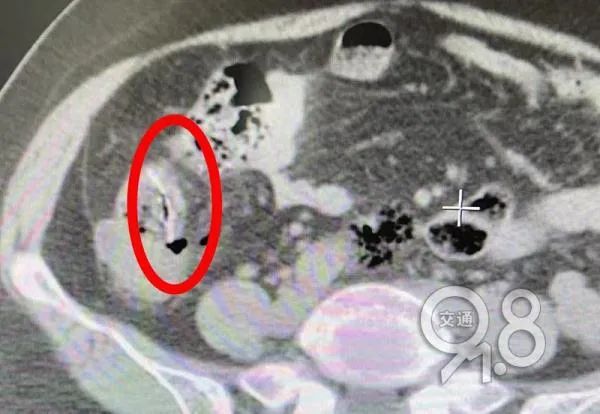

该院胃肠肛外科医师查体发现,她腹部压痛、反跳痛明显,肚子僵硬,血液检查显示白细胞严重超标,是腹膜炎的信号。腹部CT发现,胡大姐的小肠腔内有条状异物。

横扎在小肠上的一根鱼刺

综合患者描述,医生判断其体内异物就是鱼刺,安排腹腔镜探查。在术中发现,胡大姐腹腔内已产生大量脓性腹水,回肠部有一根硕大的鱼刺穿破小肠,露出尖头,穿孔处的肠壁及系膜高度水肿。

刺穿小肠的鱼刺